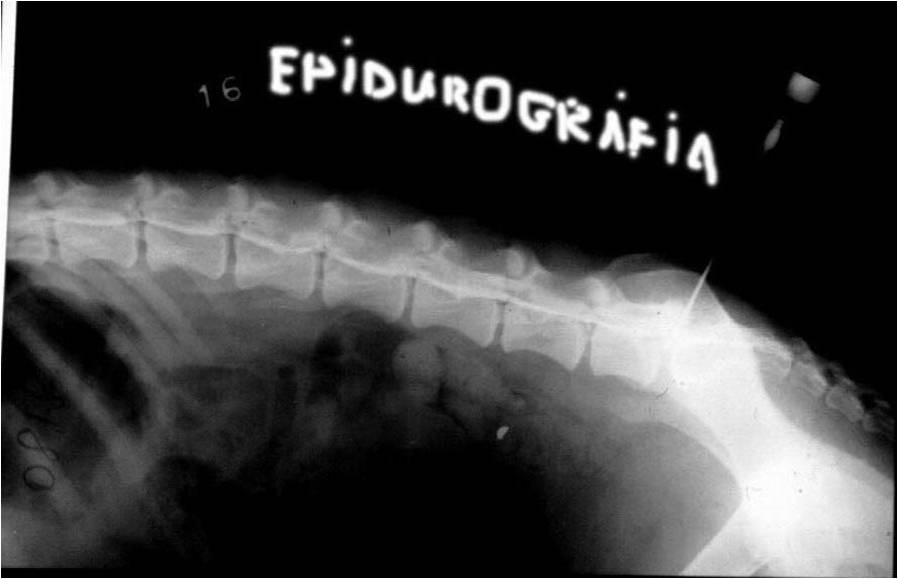

L7-S1 punctio: epidurográfia, speciális célra,

főleg cauda equina syndroma igazolására

Epidurogram lumbalis szakaszon